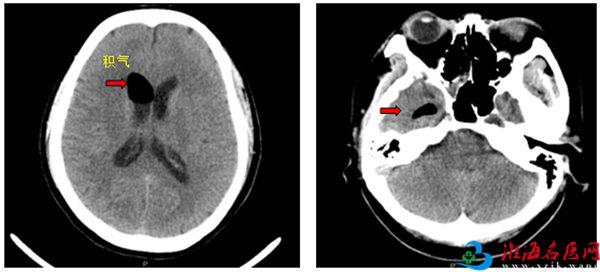

影像检查示患者颅内积气

外院CT检查报告显示,L女士颅内有积气,还有一个脑膜瘤。颅内积气又称外伤性气颅,是颅外或含气骨内气体进入颅内而形成,为头部外伤或开颅手术的一种并发症。“我既没受过外伤,也没做过手术,怎么会有颅内积气?”L女士感到很诧异。因病情复杂,且当时L女士已有较重的颅内感染,医生建议将其收入ICU先行抗感染,稳定后再联系其他医院专家手术治疗。

听说要进ICU,L女士和家人都吓坏了,多方打听后,慕名来到徐州一院,找到神经外科知名专家、名誉科主任徐锋教授,寻求帮助。徐锋根据患者的影像资料,结合病史,证实患者颅底骨质漏口是造成颅内积气和多年清水“鼻涕”持续流淌的原因。当听说这些年鼻腔里淌的不是鼻涕而是脑脊液时,L女士和家人都大吃一惊。